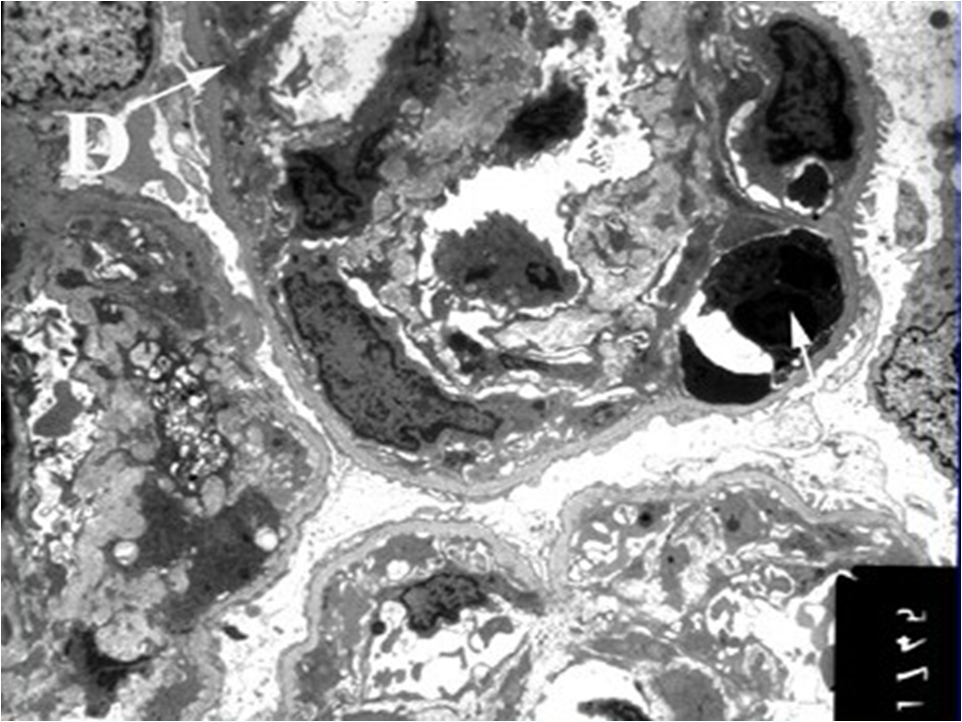

电镜下系膜区和内皮下可见电子致密物沉积(图5-4-3)。 该病理类型约占我国原发性NS的10%~20%。本病男性多于女性,好发于青壮年。约1/4~1/3患者常在上呼吸道感染后,表现为急性肾炎综合征;约50%~60%患者表现为。NS,几乎所有患者均伴有血尿,其中少数为发作性肉眼血尿;其余少数患者表现为无症状性血尿和蛋白尿。肾功能损害、高血压及贫血出现早,病情多持续进展。50%~70%病例的血清C3持续降低,对提示本病有重要意义。 本病所致NS治疗困难,糖皮质激素及细胞毒药物治疗可能仅对部分儿童病例有效,成人疗效差。病变进展较快,发病10年后约有50%的病例将进展至慢性肾衰竭。